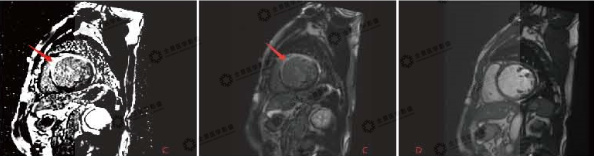

▲电影序列

全心变大,红色箭头:变薄心肌

▲A:延迟强化序列 B:电影序列

红色箭头:显示二腔心界面中,前壁、心尖部和后壁环死心肌范围及透壁程度

▲C:延迟强化序列 D:电影序列

红色箭头:中央部短轴显示前壁及前间隔壁、下间隔壁的梗死范围及透壁程度